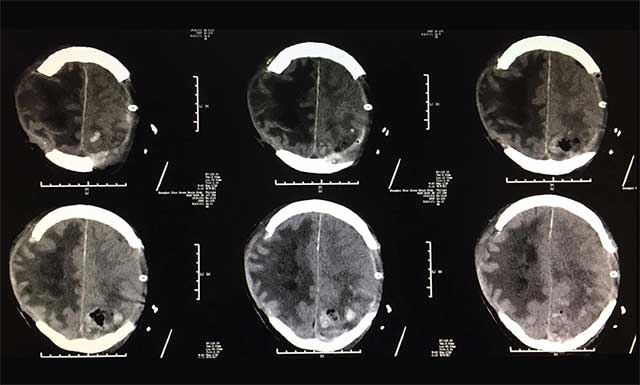

▲术后患者出血情况较前明显好转

术后患者影像显示,颅内出血较前明显好转,看到已经度过危险期的患者,家属感慨万分,患者女儿更是感激的说:“这次幸好遇到蓝十字如此专业负责的医生团队,从发现父亲情况异常,到会诊定方案,再到手术的进行,专家争分夺秒,救治及时,我父亲才得以保住了性命。”